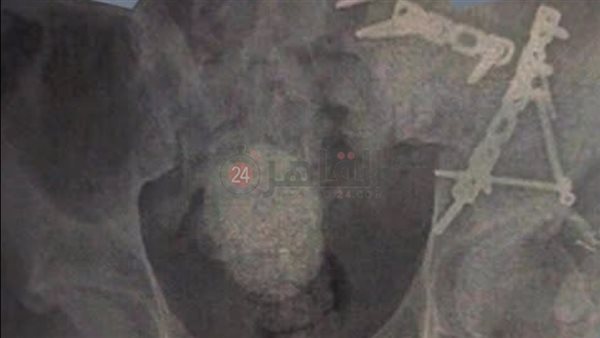

واستقبل المجمع حالة طبية حرجة تعاني من كسر معقد في عظام الحوض، مصحوبًا بكسر آخر في المفصل العجزي الحرقفي، وهي من الإصابات التي تتطلب دقة متناهية في التشخيص والتدخل الجراحي نظرًا لحساسية الموقع وقربه من الأعصاب والأوعية الدموية الرئيسية.

ونجح الفريق الطبي المتميز بقسم جراحة العظام في إجراء الجراحة بنجاح باهر، حيث تم رد الكسور وتثبيتها باستخدام تقنيات متطورة تضمن أعلى معايير الجودة والأمان.